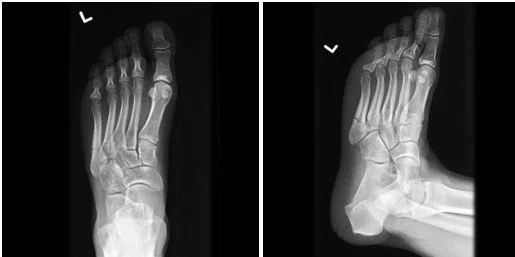

Image 1. Plain radiograph of the left foot. Case courtesy of Frank Gaillard, Radiopaedia.org

This is a fracture of the base of the fifth metatarsal where the 4th and 5th intertarsal junction occurs, which is classified as a Jones fracture.

Pearl: The location of the fracture in the fifth metatarsal is extremely important and affects treatment. Lawrence and Botte developed classifications which used three zones. Fractures that are more proximal are Zone 1. These are pseudo-Jones or tuberosity avulsion fractures. Zone 2 is the intertarsal junction, These are Jones fractures. Zone 3 is the most distal and commonly involves diaphyseal stress fractures (2).